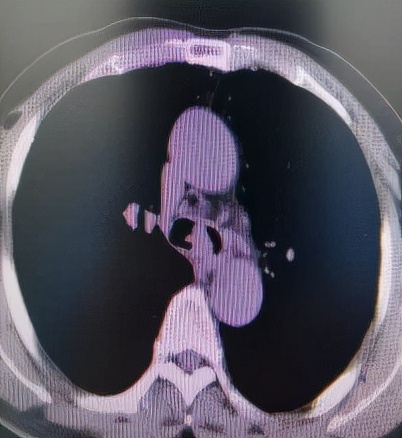

经过充分细致的各项准备工作,手术如期进行。麻醉科刘淑杰副主任医师给患者经喉罩套气管插管(8mm),在充分气道保护下插入电子支气管镜观察病变,隆突区可见菜花状新生物,表面凹凸不平,血供较丰富,新生物累及左主支气管导致管腔狭窄约80%,新生物也累及右主支气管导致管腔狭窄约60%,手术难度比预计还要高。因病变刚好位于隆突区,操作稍有不慎,很容易将隆突穿漏。术中于世寰主任熟练地交替应用各种设备,于新生物处反复施以激光蚀刻、电切刀电切、圈套器套取、二氧化碳冷冻冻取等操作,削瘤过程中的出血,应用APC充分予以止血,完美的完成了削瘤手术。术后患者很快苏醒,醒后患者的第一反馈就是呼吸顺畅多了。

削 瘤 过 程